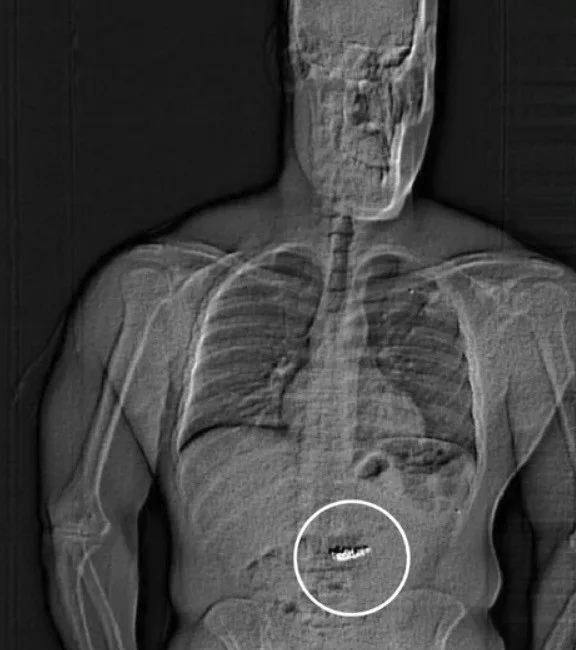

Уже в тюрьме мужчина неожиданно спросил персонал, не накажут ли его за то, что в его желудке. Гилдеру провели сканирование тела, в ходе которого детективы обнаружили инородные предметы в пищеварительном тракте.

«Предполагается, что эти инородные предметы являются украденными серьгами Tiffany & Co. Однако подтверждение подлинности невозможно до тех пор, пока они не пройдут через организм Гилдера», — говорится в отчёте.